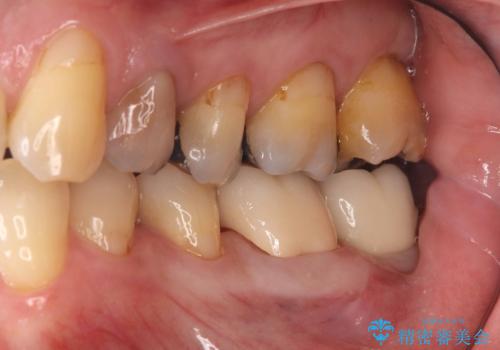

また、左下6番は銀歯と虫歯を除去した後、見た目や適合性に優れたオールセラミッククラウンで修復を行いました。

インプラントとセラミック治療を組み合わせることで、見た目も自然で噛み心地の良い状態を回復することができ、患者様にも大変ご満足いただけました。